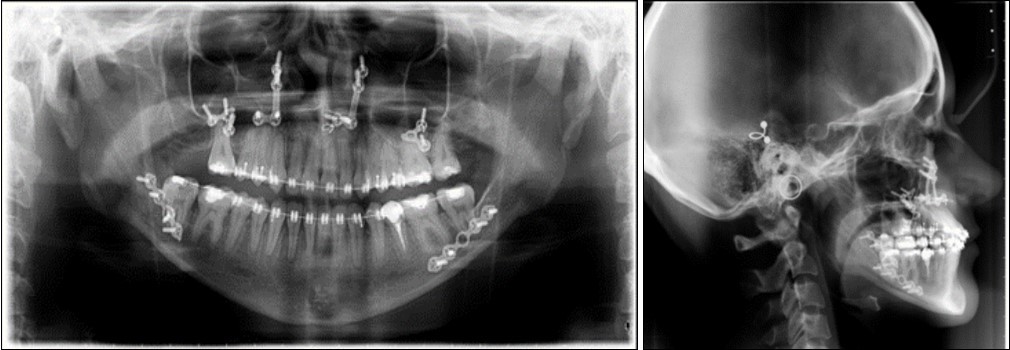

Post-surgical orthodontic treatment was started 4 weeks after the surgery. Wearing of bilateral box elastics was recommended in order to improve interdigitation. (Figure 6) The orthodontic treatment was finished on 0.019x0.025 SS archwires. Post-surgery cephalometric analysis revealed an increase in SNA value by 4 degrees (SNA 82 degrees) and a decrease in SNB value also by 4 degrees (SNB 79 degrees). The patient was now in a skeletal class I, with ANB 3 degrees. An examination of the soft tissue on the radiograph reveales a better relation between the upper and lower lip. (Figure 7).

Figure 6.Post-surgical intraoral photographs, with bilateral box elastics

Figure 7.Post-surgical panoramic and lateral cephalometric radiograph.